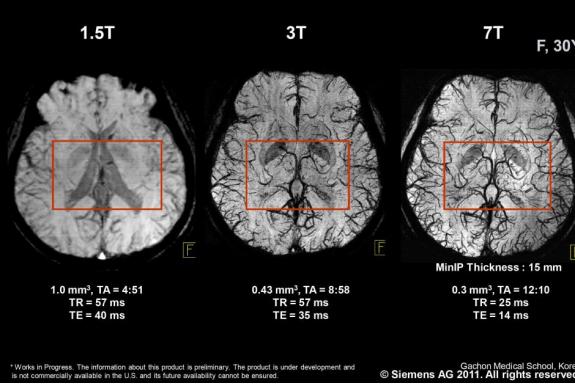

In the past years there have been many advances in imaging technologies, paving the way for the highest resolution and image quality to date. At one time, medical professionals thought that 1.5 T, and after that 3 T would be the pinnacle of MRI field strength. When 7 T was developed, nobody ever thought it could be used for anything other than research purposes. Now, several companies have taken interest in developing 7 T clinical MRI systems for use in large hospitals.

3 T can be compared to a sports car as it has plenty of horsepower, torque and is featurepacked. However problems occur when the 3 T sports car mutates into a 7 T Formula 1 racing car, which makes daily use even more challenging. The major question is under what circumstances are the increased costs of 7 T and the inherent limitations in coverage and safety outweighed by diagnostic benefits.

It is important to remember that although there are relatively few studies directly comparing 1.5 T, 3 T and 7 T, it is generally considered that higher field strength does not necessarily mean higher diagnostic accuracy for all diseases and abnormalities. This means that 7 T MRI will fill a specific niche in the market for certain sequences and imaging methods. They include: 31P MR spectroscopy (31PMRS), which can be used as a noninvasive tool for measuring the relative intracellular concentrations of several phosphorus metabolites in different organs.